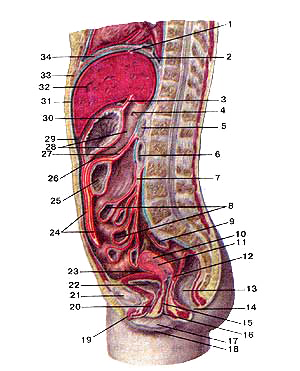

Топография внутренних органов и брюшины в брюшной полости женщины

Срединный сагиттальный разрез.

I-венечная связка печени;

2-верхнее сальниковое углубление;

3-печеночно-желудочная связка;

4-зонд в сальниковом отверстии;

5-гюджелудочная железа;

6-двенадцатиперстная кишка;

7-корень брыжейка тонкой кишки;

8-тонкая кишка;

9-сигмовидная кишка;

10-матка;

11-полость матки;

12-прямокишечно-маточное углубление;

13-прямая кишка;

14-задний проход;

15-влагалише;

16-отверстие влагалища;

17-малая половая губа;

18-болышая половая губа;

19-клитор;

20-мочеиспускательный канал;

21-лобковый симфиз;

22-мочевой пузырь;

23-пузырно-маточное углубление;

24-большой: сальник;

25-поперечная ободочная кишка;

26-нижнее сальниковое углубление;

27-брыжейка поперечной ободочной кишки;

28-сальниковая сумка;

29-преджелудочная сумка;

30-желудок;

31-печеночная сумка;

32-печень;

33-мечевидный отросток грудины;

34-диафрагма.